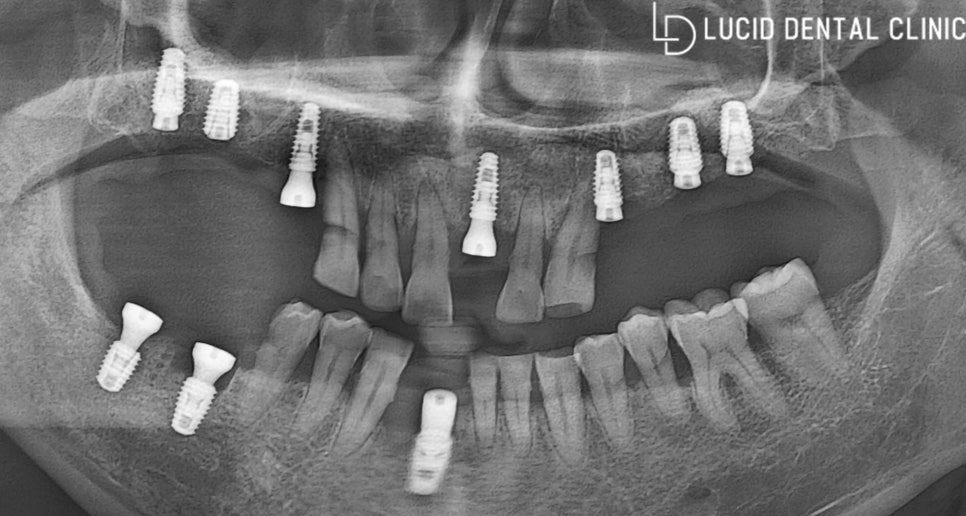

이제 정밀한 치료 계획을 수립해 볼까요?

우선 자연치를 최대한 보존하는 것을 중점으로

문제가 되고 있는 치아만 모두 발거하고,

픽스처를 즉시 식립하기로 했는데요.

최대한 부기와 통증을 줄여주고,

정밀하고 안정된 수술이 가능하도록

컴퓨터 분석 프로그램을 이용하기로 했습니다.

마취를 시작으로 본격적인

치료 과정을 진행해 봤는데요.

치아 발거 후 필요한 곳에

골이식을 시행하였습니다.

치아 뿌리 방향대로 접근하여

상악동을 들어 올린 후,

인공 뼈 재료를 채워 넣었는데요.

골이식을 마치자마자

컴퓨터 분석 자료를 토대로

빠르게 픽스처를 식립하였습니다.

픽스처 내부로 외부 물질이 들어오는 걸

어버트먼트를 체결하여 막아 줄 건데요.

어버트먼트는 최종 보철을 올릴 때

적당한 치은 형태를 만들고,

최종 보철과 매끄럽게 연결되도록

도와주기 때문에 체결하고 있습니다.

환자는 상, 하악 전체를 시행했기 때문에

회복 기간이 조금 길 것으로 판단됩니다.